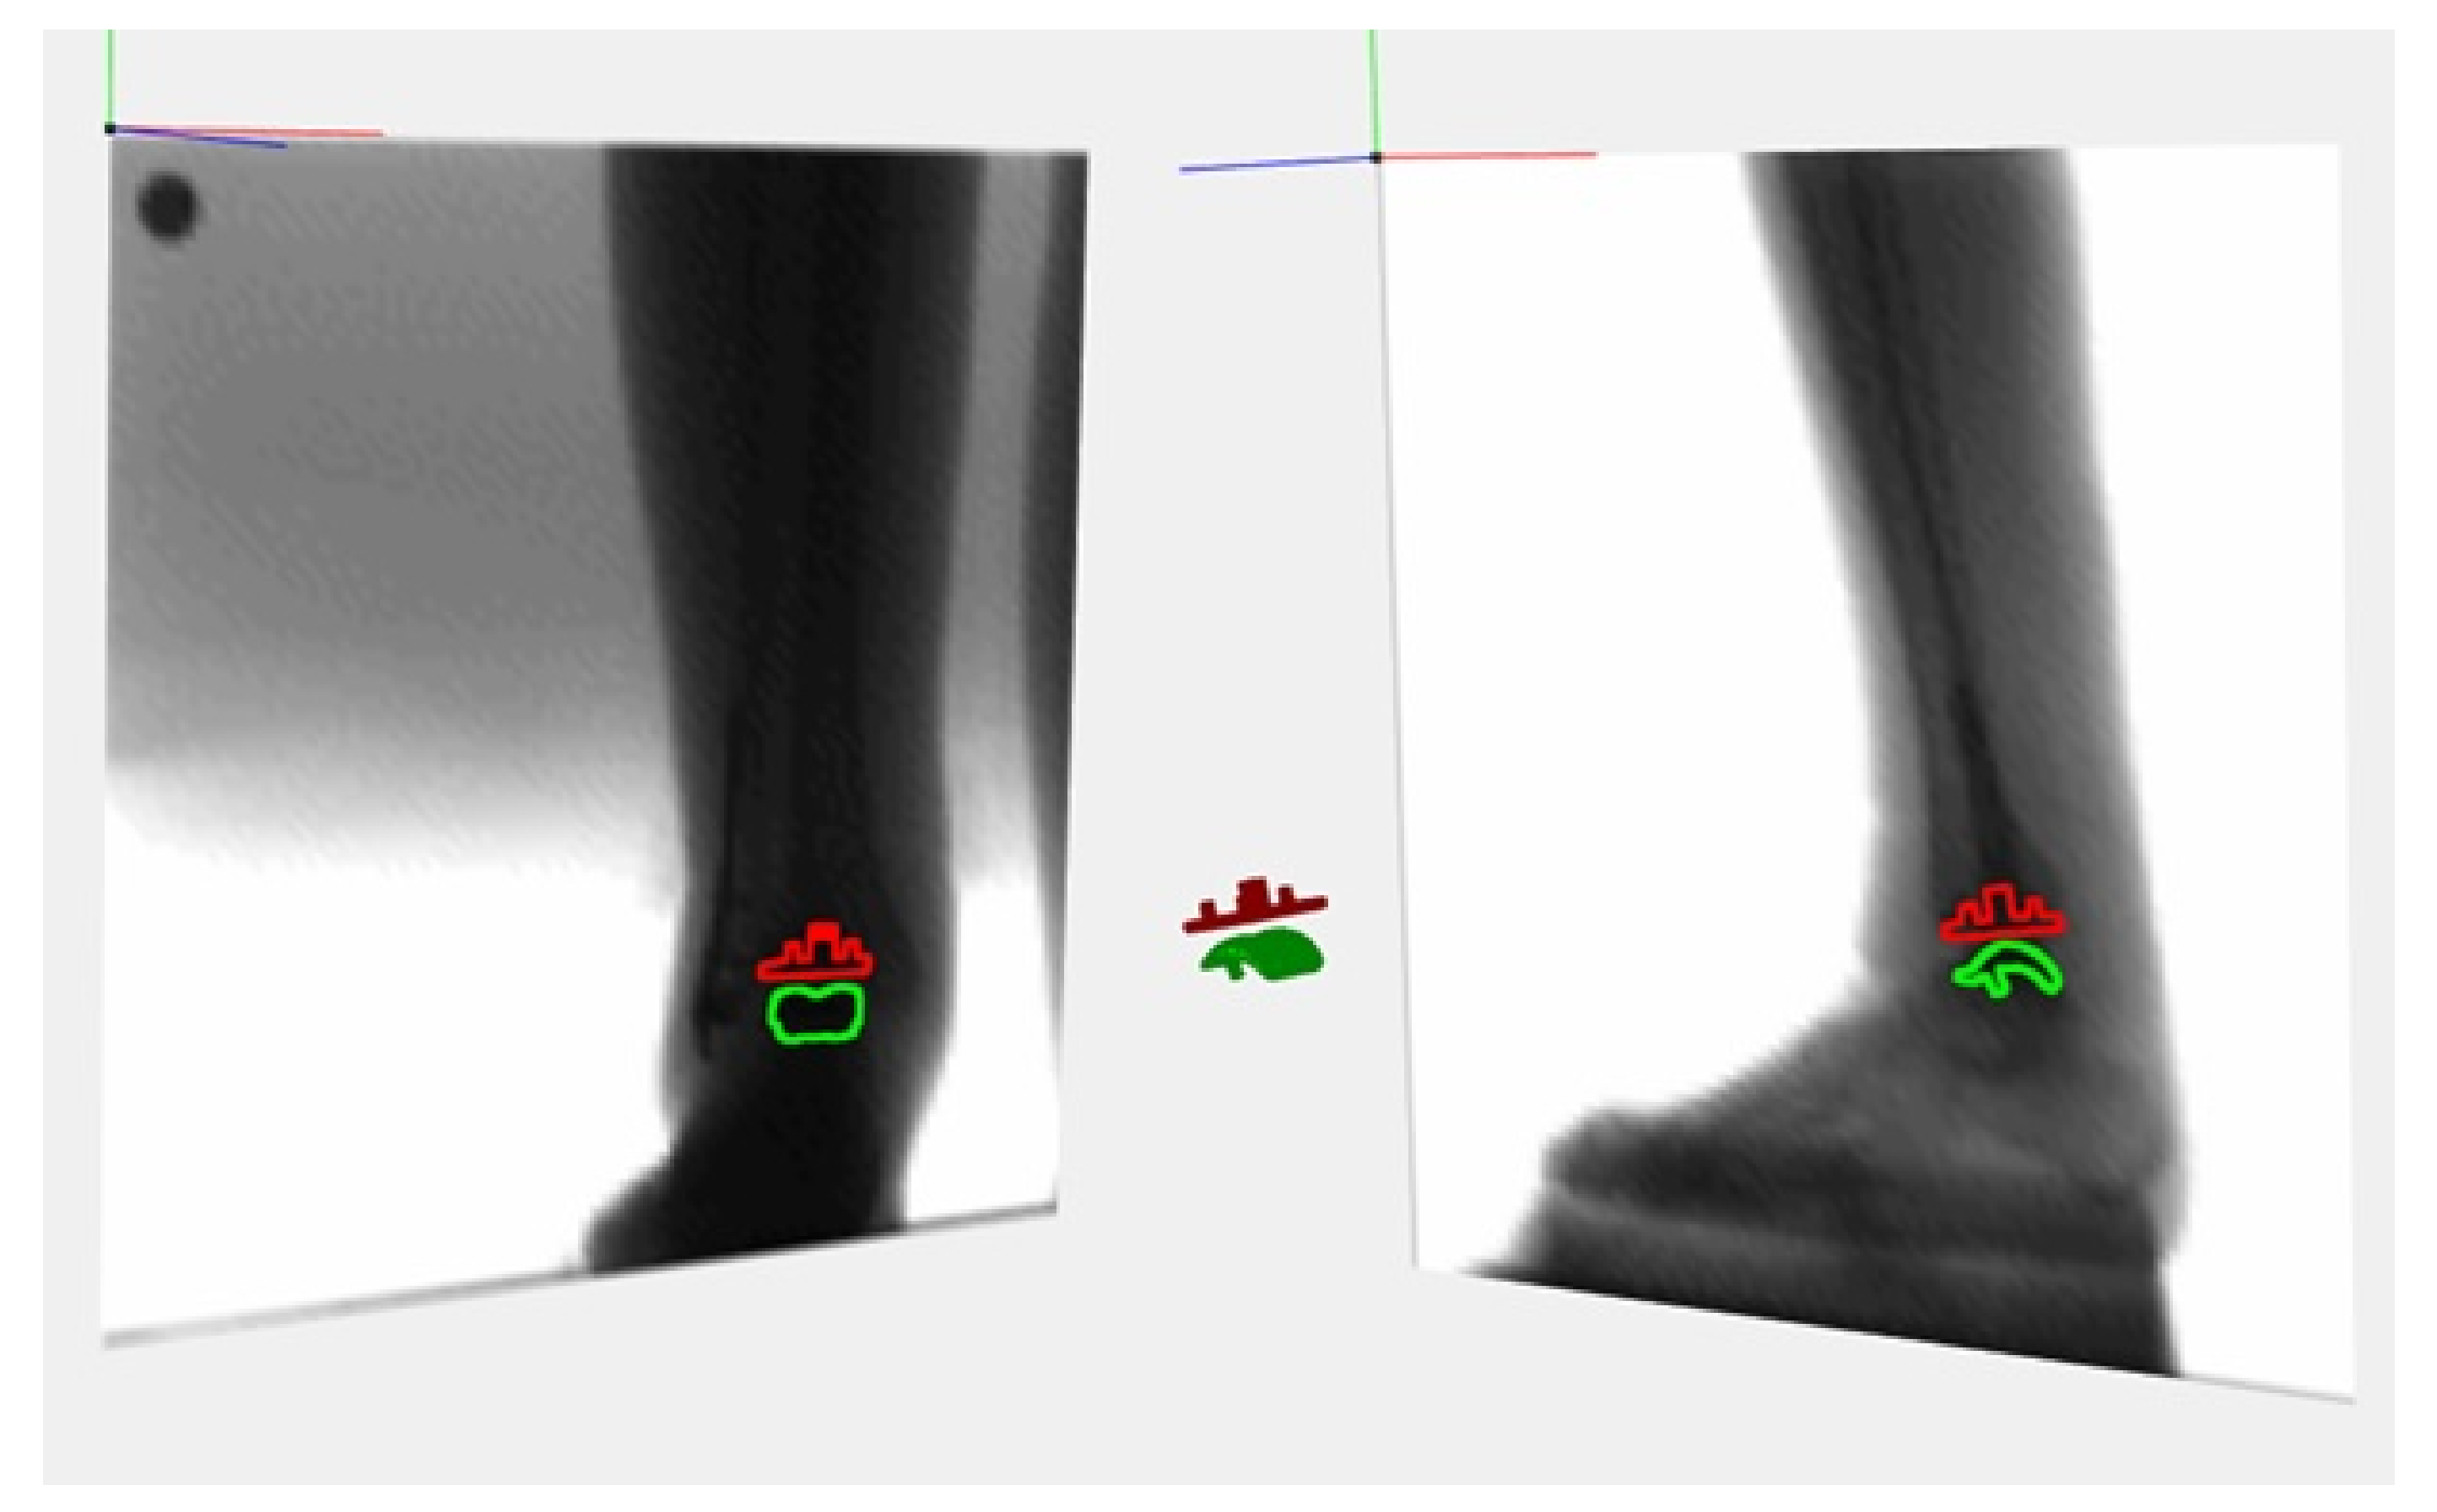

2.4. Data Collection and Measures